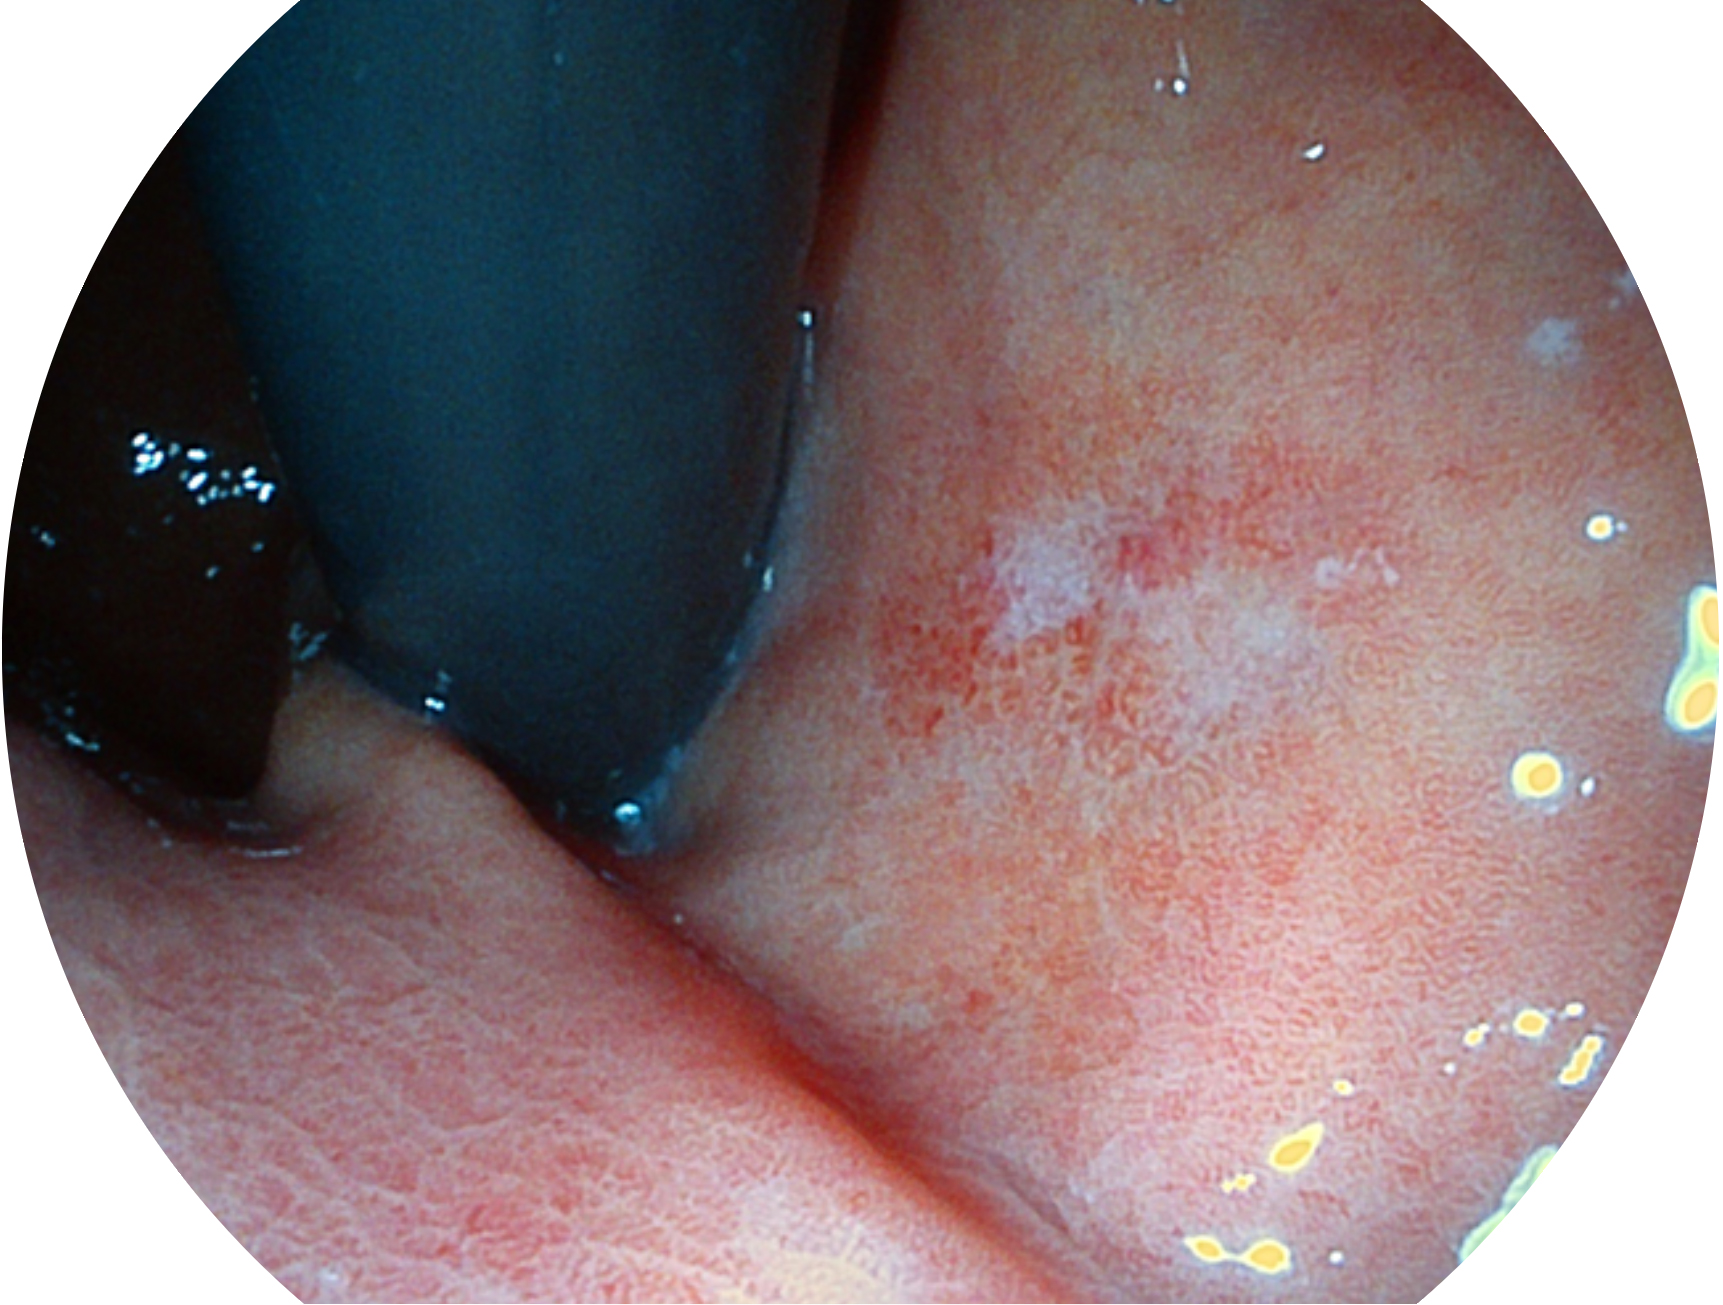

百老汇电子游戏官网新开发的内镜染色技术,主要是基于多波长LED 光源的开发,VLS-55Q 四波长LED 光源是由四个不同颜色的LED光按照相应照明模式所规定的特定发光比例进行合束后形成,合束后形成的照明光的光谱由红光、绿光、蓝光及蓝紫光这四个不同的波段范围构成。具有更高光谱自由度,通过光谱比例的控制,实现了聚谱成像技术,英文全称为“Spectral Focused Imaging, SFI”,缩写为“SFI”和光电复合染色成像技术,英文全称为“Versatile Intelligent Staining Technology, VIST”,缩写为“VIST”。